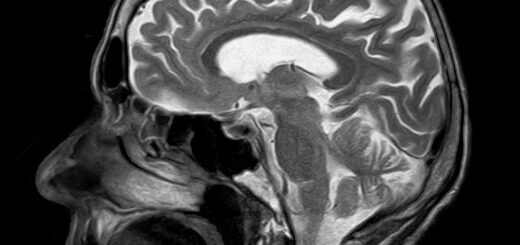

Hi, and thanks for stopping by! I’m a PhD candidate in Medical Sciences at the University of Brasília, researching the Neuroscience of Ageing (e.g., how the brain changes over time and how we can support its health). My work spans cognitive decline, sleep, and brain clearance systems, with a special focus on using data science, neuroimaging, and computational tools to reveal new insights. If you’re into ageing research, neuroscience, or science-meets-tech curiosity, you’re in the right place! 😉

- Magnetic Resonance Imaging